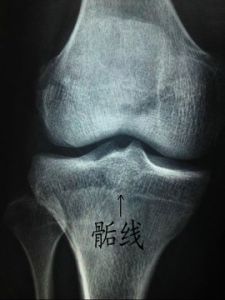

骨垢線長骨的兩端膨大,稱為骺.幼年時,骨幹與骺之間有透明軟骨,成年後軟骨骨化,骨幹與骺融為一體,其間遺留的痕跡,叫骺線.

長骨的兩端膨大,稱為骺。幼年時,骨幹與骺之間有透明軟骨,成年後軟骨骨化,骨幹與骺融為一體,其間遺留的痕跡,叫骺線。